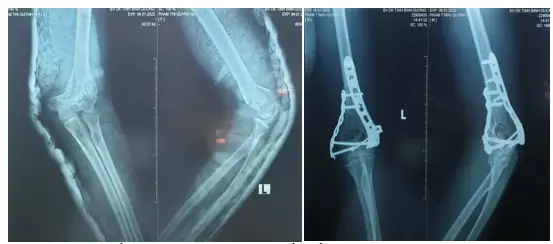

Kết hợp xương gãy liên lồi cầu xương cánh tay